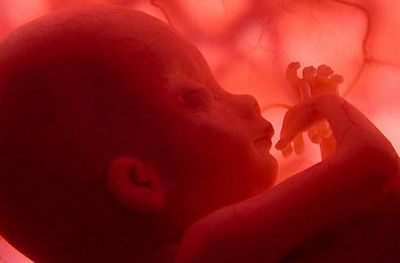

L’adattamento all’ambiente extrauterino è uno dei compiti principali che il bambino si trova ad affrontare alla nascita e durante i primi mesi di vita. ...